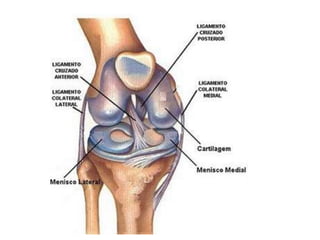

3-Capsula articular: É na sua forma mais simples um tubo, cujas extremidades estão inseridas ao redor das superfícies articulares. É composta por duas camadas, uma externa constituídas de tecido fibroso, e uma interna, a camada ou a membrana sinovial. 4- Ligamentos: São fortes cintas ou membranas, composto de tecido fibroso branco, que unem os ossos entre si. Geralmente são praticamente inelásticos. Podem ser subdividos de acordo com sua posição em: peri ou extra-articulares.

5-Disco e meniscos articulares: São placas de fibrocartilagem ou tecido fibroso denso embutidos entre das cartilagens articulares e dividem a cavidade articular parcial ou completamente em dois compartimentos, permitem maior amplitude e variedade de movimento. 6- Cartilagem marginal: É um anel de fibrocartilagem que rodeia a borda de uma cartilagem articular. Amplia a cavidade e contribui na prevenção de fraturas da borda articular.

3-Capsula articular: Éna sua forma mais simples um tubo, cujas extremidades estão inseridas ao redor das superfícies articulares. É composta por duas camadas, uma externa constituídas de tecido fibroso, e uma interna, a camada ou a membrana sinovial. 4- Ligamentos: São fortes cintas ou membranas, composto de tecido fibroso branco, que unem os ossos entre si. Geralmente são praticamente inelásticos. Podem ser subdividos de acordo com sua posição em: peri ou extra-articulares.

5-Disco e meniscosarticulares: São placas de fibrocartilagem ou tecido fibroso denso embutidos entre das cartilagens articulares e dividem a cavidade articular parcial ou completamente em dois compartimentos, permitem maior amplitude e variedade de movimento. 6- Cartilagem marginal: É um anel de fibrocartilagem que rodeia a borda de uma cartilagem articular. Amplia a cavidade e contribui na prevenção de fraturas da borda articular.